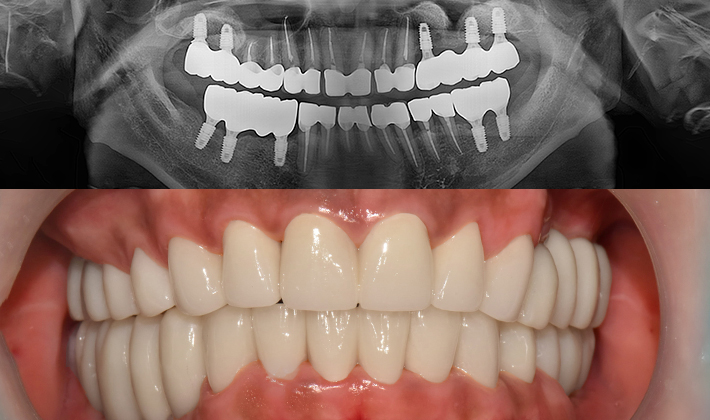

치과가 무서워 10년 동안 미뤄온 임플란트 수술 그 결과는?